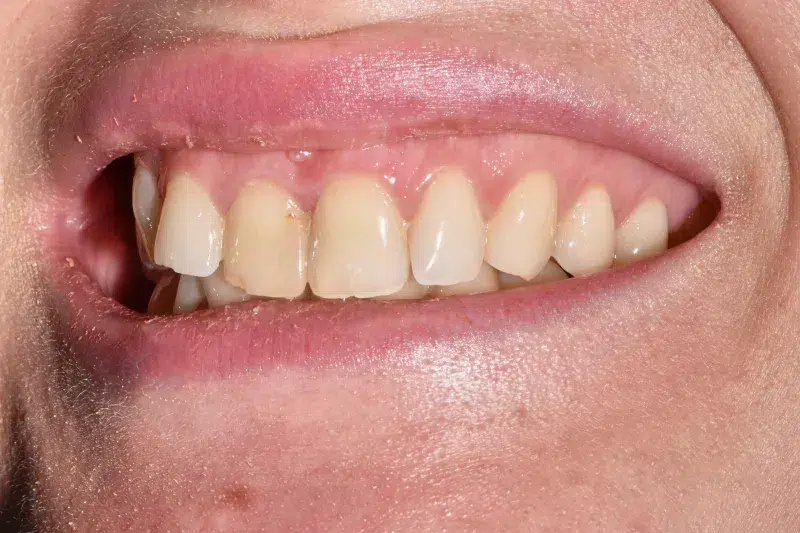

Implant dentar cu implantare imediată în 24H – Fast and Fixed

Provocarea acestui caz din punct de vedere chirurgical a fost obținerea unei stabilități osoase suficiente astfel încât pacienta putând să primească dinți ficși provizorii în 24 ore, osul fiind extrem de slăbit în urma unui accident. Provocarea din punct de vedere estetic a fost de a uniformiza culoarea noului incisiv primit cu culoarea identică a incisivului vecin.

Pacienta a beneficiat de implant titan Bredent, o coroană de zirconiu ceramic pentru estetică, evaluare boală parodontala și chiuretaje gingivale cu laser.

Termen de finalizare 2 săptămâni de la amprentarea finală.